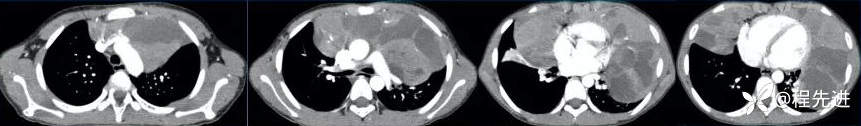

增强